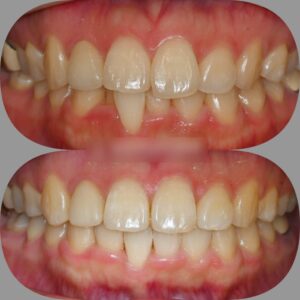

반갑습니다, 면목역 치과 글로리의 김정은 대표원장입니다. 교정이 필요한 순간들이 꽤 여럿 있습니다. 가지런하지 못한 치열을 가졌을 때도 있고, 때로는 맞지 않은 교합 관계의 문제, 그리고 뻐드러진 치열을 가질…

전체적으로 브라켓을 붙여 이를 이동시키는 치아교정은 비용뿐만 아니라 심리적 부담감도 따르기 마련입니다. 저희 글로리 신내동 치과 를 내원하시는 환자들께서도 마음은 먹고 오셨지만, 시작하기에 앞서 이런 걱정거리들을 얘기해 주시곤…